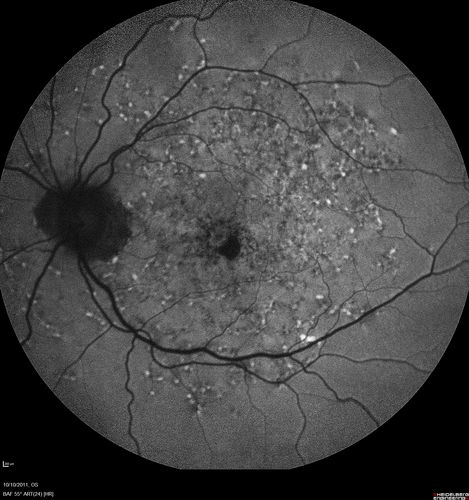

Stargardt's Macular Dystrophy ABCA4 positive

Fundus Autofluorescence shows central atrophy with Hyper FAF pisciform triradiate lesions. Images show some progression over 3 years of macular dystrophy.

Stargardt's Macular Dystrophy - Heterozygous ABCA4 T>C substitution at potisoin -10 of intro 38